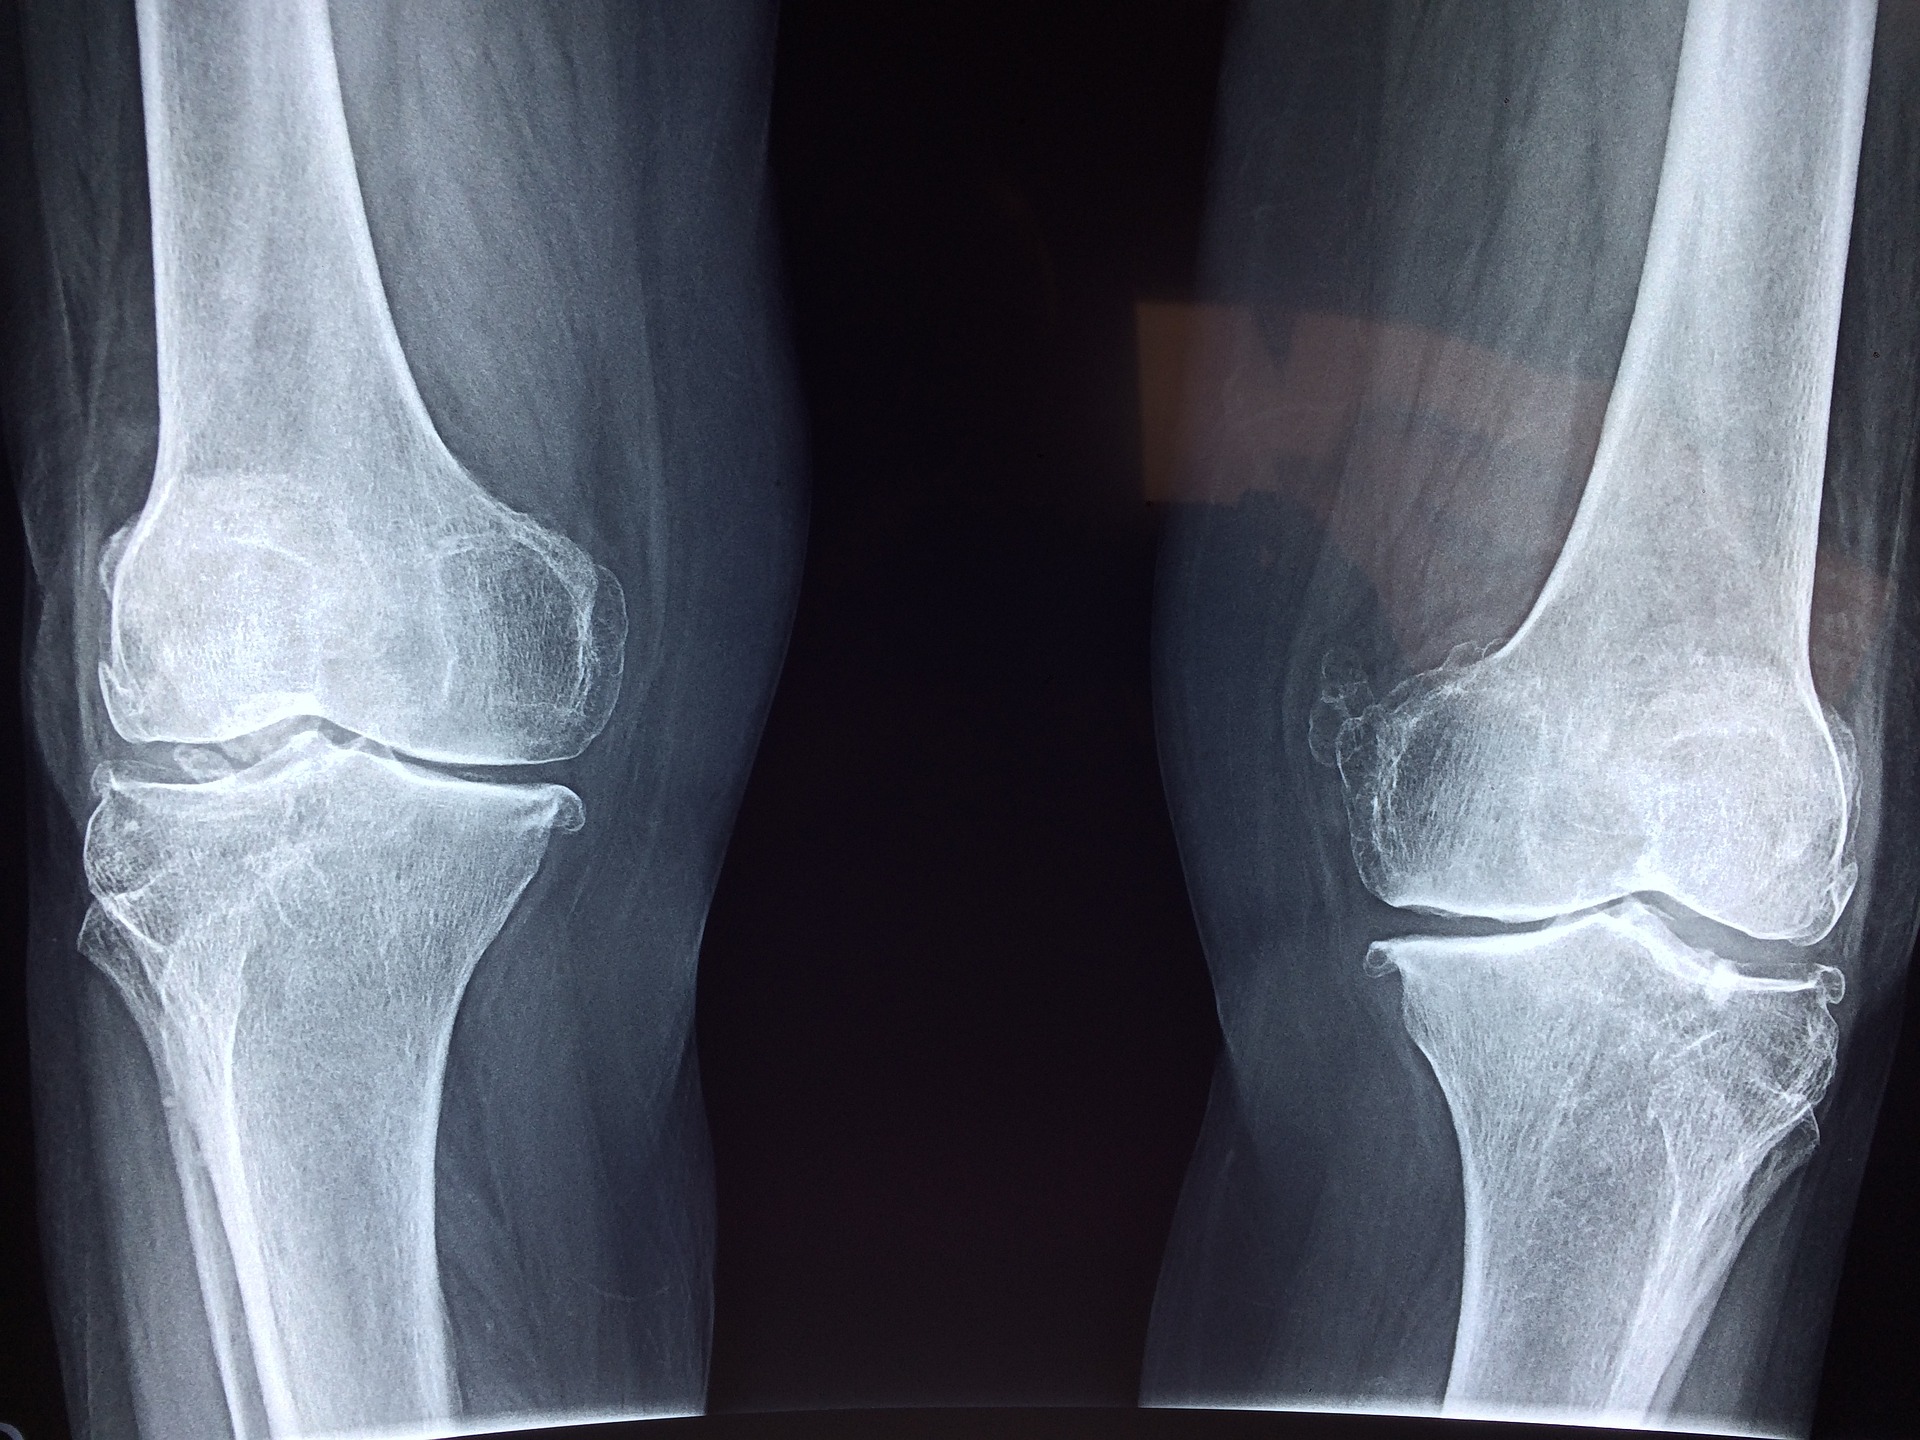

연골 손상과 퇴행성 관절염은 우리 몸의 건강한 기능을 방해하는 질환입니다. 연골은 신체적인 부담 및 나이로 인해 손상이 발생할 수 있는데, 이러한 손상은 상대적으로 긴 시간 동안 진행되며, 적극적으로 예방 조치를 취하지 않는다면 연골의 손상이 계속 진행되어 퇴행성 관절염으로 진행되게 됩니다.